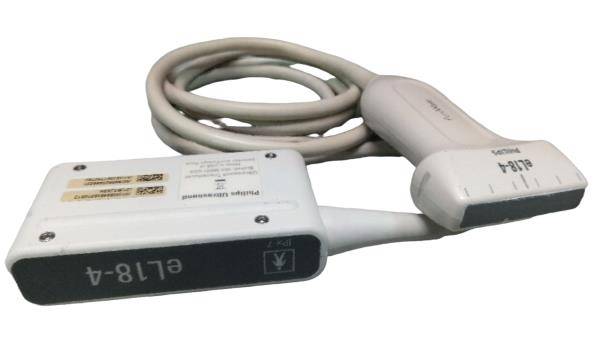

DIAGNOSTIC ULTRASOUND MACHINES FOR SALE

Ultrasound Scanner Monitor With Linear Probe N 3D LCD Digital Display Portable 190891264251

Sale price$ 2,076.23

Regular price$ 2,531.99